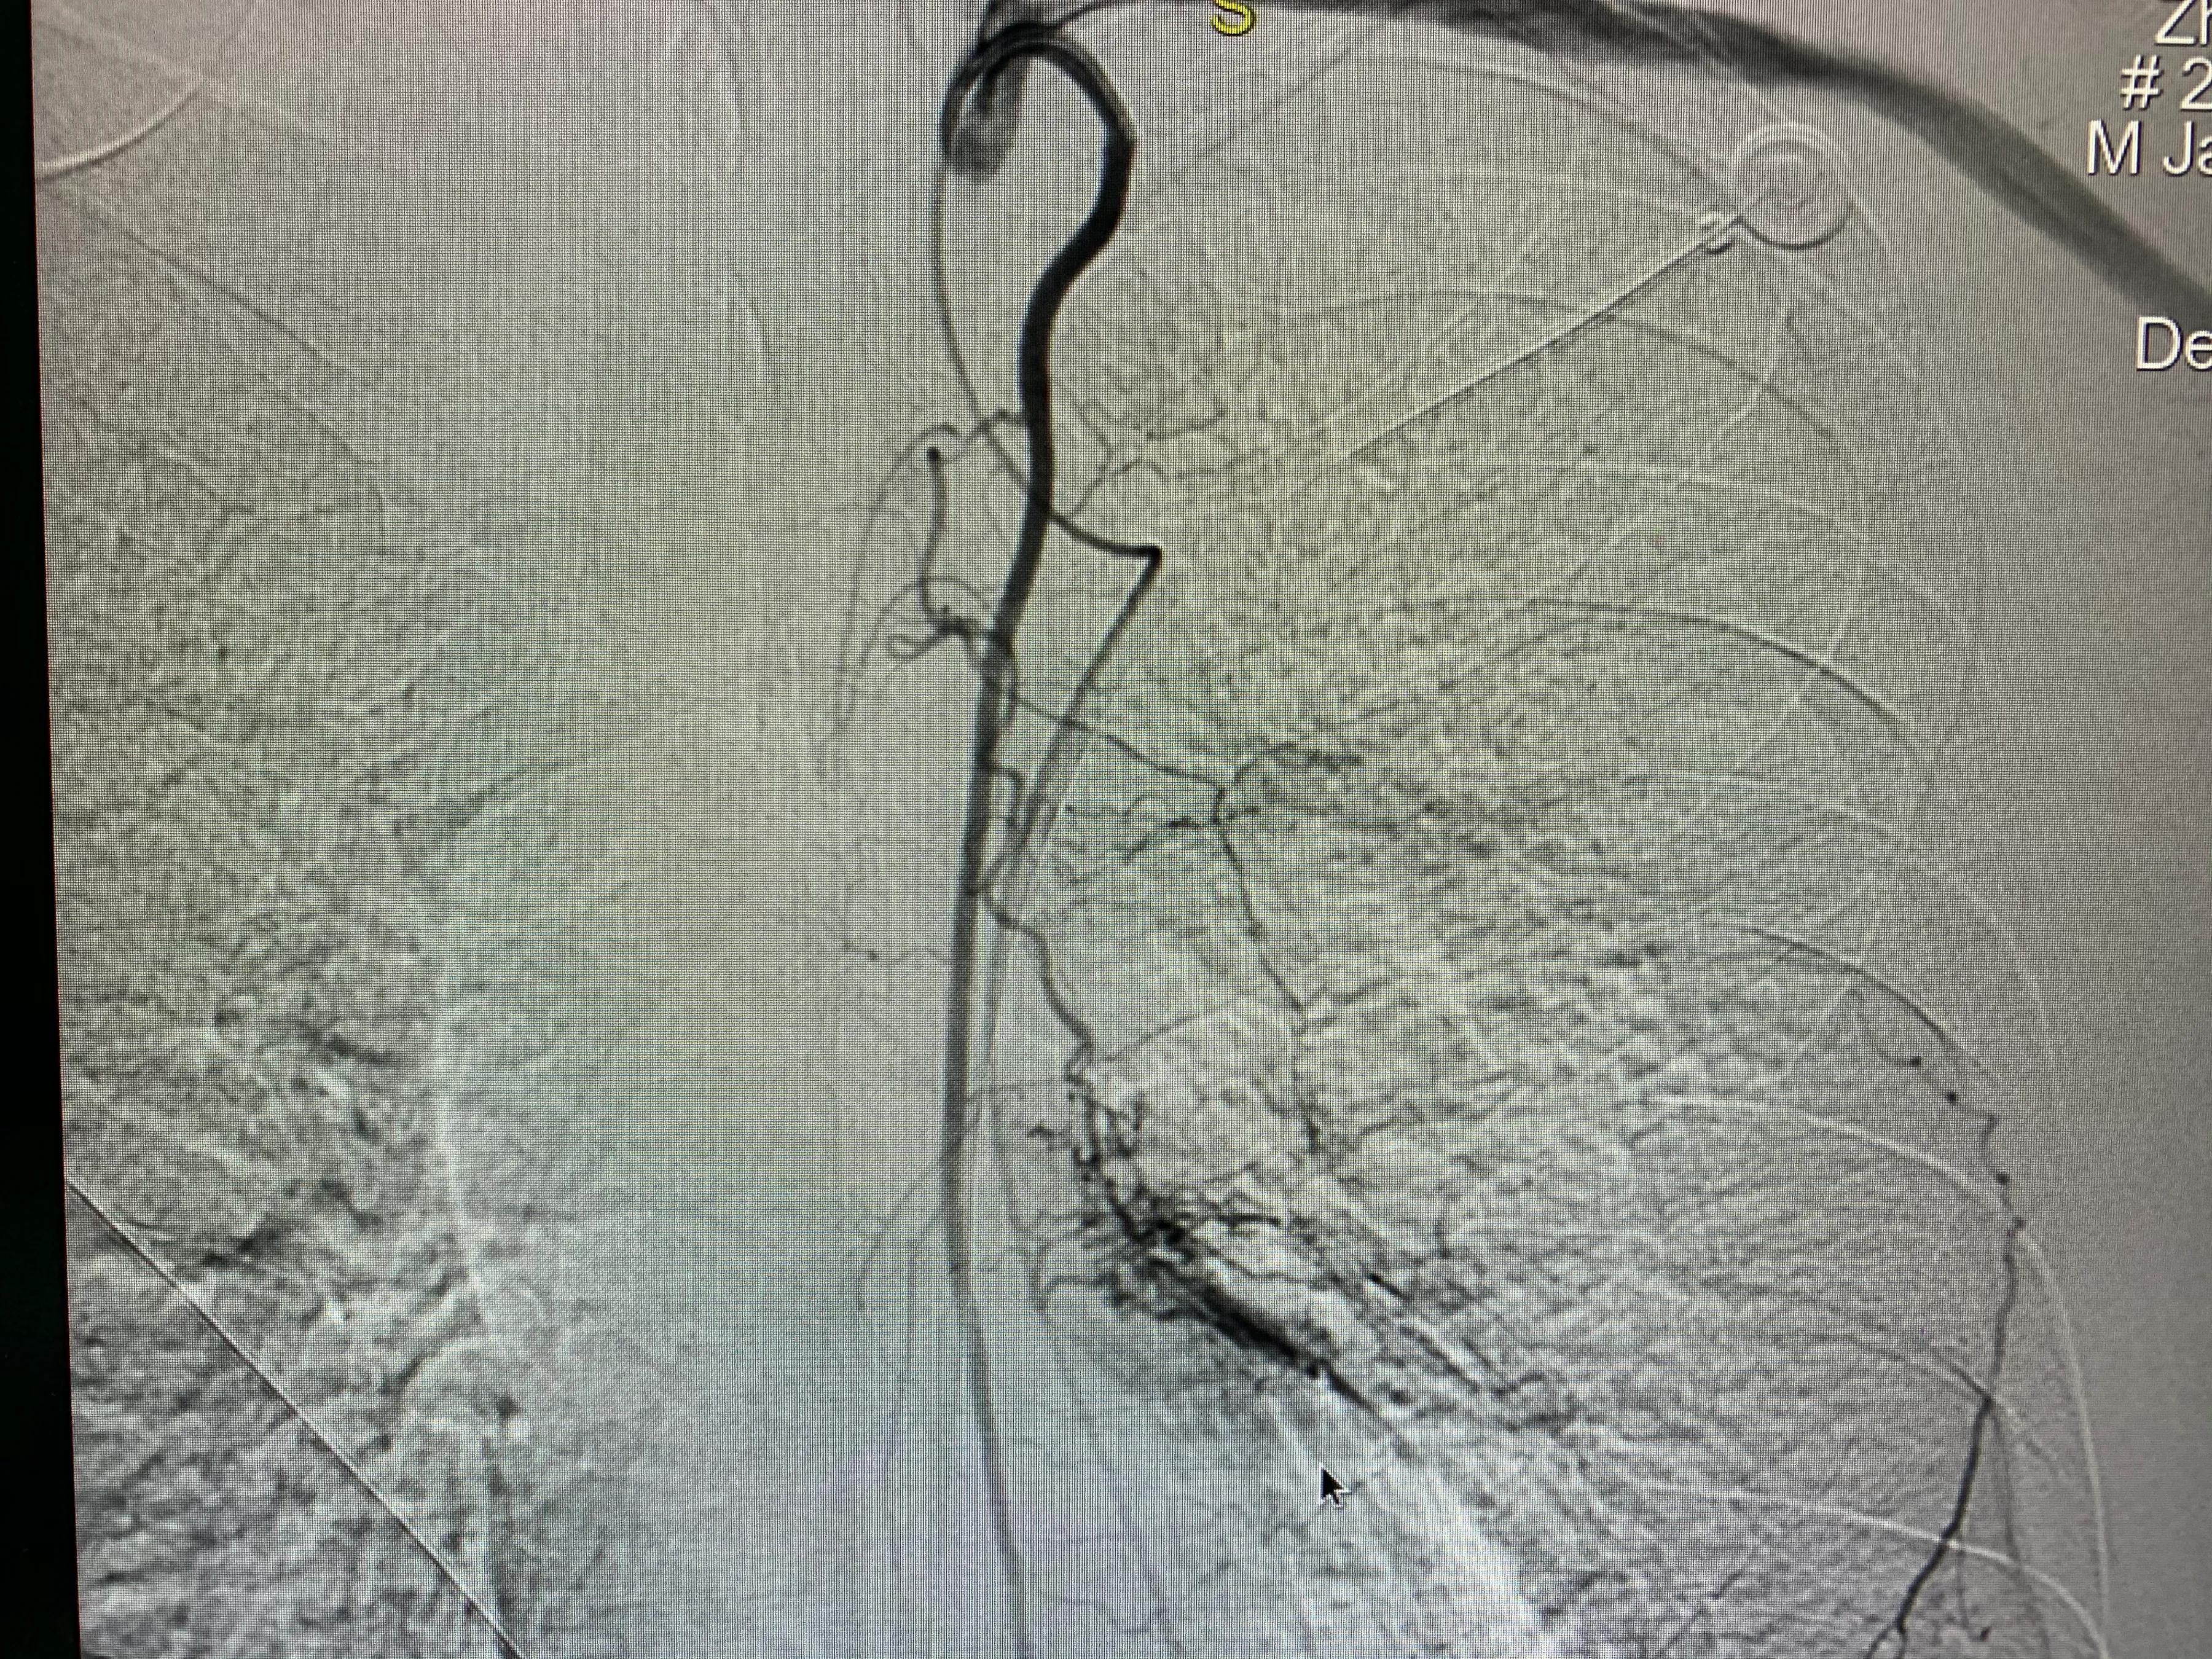

老年男性患者,左肺腺癌,化疗期间出现了咯血,术中可见左侧支气管动脉、左侧多支肋间动脉及左侧胸阔内动脉均参与肿瘤的血供,并可见以上动脉-肺动脉瘘,经肿瘤供血动脉灌注化疗药并且进行栓塞,术后未再出现咯血,一个月复查ct提示肿瘤较前明显减小,阻塞症状较前缓解。微创介入即经导管灌注化疗栓塞治疗肺肿瘤能够有效治疗肿瘤并且缓解肿瘤引起的一系列并发症,如咯血、阻塞性肺炎等,当然,肿瘤的治疗是综合治疗,需要多学科的共同参与。